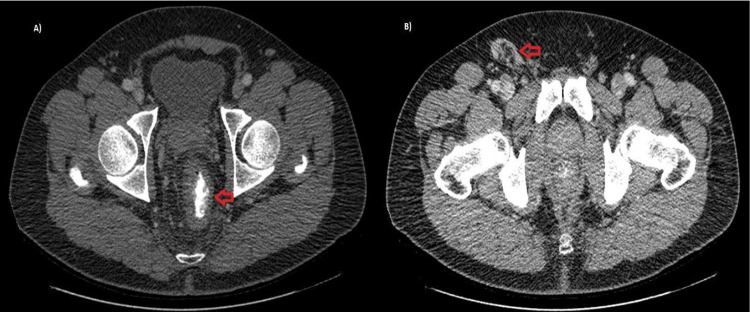

A male, 51 y-old, PLHIV whom MSM on the regular treatment of HIV was made with the combination of tenofovir, lamivudine, and dolutegravir, which is a highly active antiretroviral therapy (HAART), and the patient was indetectable for many years. This patient was HIV a long time ago using multiple treatments previously, and nowadays, CD4 180 cel/mm³ count could be a natural evolution of the disease. The patient presented a rectal bleed characterized by live blood and few quantities, rectal pain, and fever for 15 days, progressing with abdominal swelling and right inguinal lymph node. In the past medical history, an advanced HIV infection and histoplasmosis with anal and intestinal lesions were treated years ago. Rectal clinical examination revealed a painful anal edge Ulcer measuring 4 cm long. In the absence of genitourinary symptoms for STIs and the presence of systemic involvement in addition to risk factors for infectious and neoplastic diseases, the strategy was to perform complementary tests to define the etiology of the disease. The abdomen and pelvis CT with contrast demonstrated irregular parietal thickening of the distal rectum and right inguinal lymph node enlargement measuring 2.8 x 3.5 cm, suggestive of an inflammatory/infectious process (Figure 1).

Figure 1. CT abdomen and pelvis with contrast in a transversal cut in portal phase phase showing in A) asymmetric parietal thickening of the distal rectum (red arrow) and in B) inguinal region with nonspecific inflammatory/infectious right inguinal lymph node enlargement (red arrow).